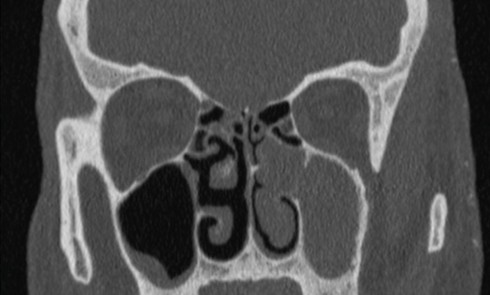

Article réservé à nos abonnés Échec du traitement d’une sinusite chronique maxillaire

Observation Il n’a pas de plainte olfactive (absence de cacosmie) ni de signes d’hyperactivité nasale. Il n’y a aucun antécédent...